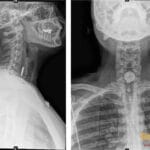

42 yr male with a history of neonatal umbilical vein catheterization presenting with hematemesis and splenomegaly.

Diagnosis: Cavernous transformation of the portal vein

- US: Anechoic tortuous collaterals or a sponge-like mass in the porta hepatis; color Doppler shows a serpiginous mixed-color pattern with hepatopetal flow and absent flow in the native portal vein.

- CT: Nonvisualization of the main portal vein trunk replaced by numerous tortuous periportal collaterals (cavernoma); may appear as a solid tumor-like enhancing hilar mass; associated signs include splenomegaly and gallbladder varices.

- MRI: Tortuous peri-hilar vessels replacing the native portal vein; MRCP may show peribiliary stenoses from extrinsic compression by collaterals (portal cavernoma cholangiopathy).

- Signs: Portal cavernoma: A sponge-like mass or tangle of enhancing vessels in the porta hepatis representing dilated periportal collaterals.